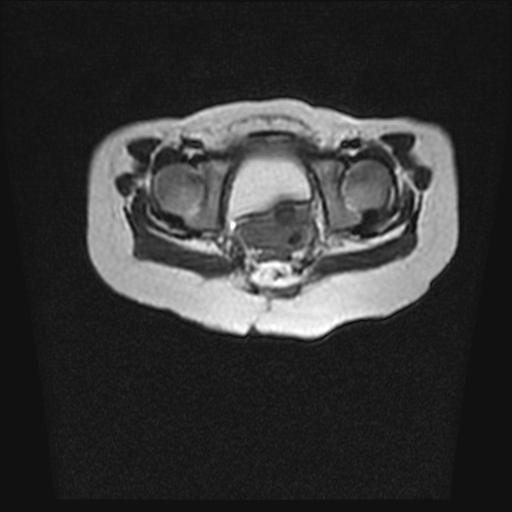

四个月的女婴,ct示脊膜膨出.

脊柱裂、脊膜膨出,请结合临床除外皮毛窦。

脂肪脊髓脊膜膨出

脊柱裂、脊膜膨出